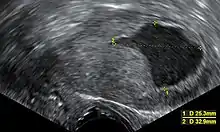

An ultrasound image showing an endometrial fluid accumulation (darker area) in a postmenopausal uterus, a finding that is highly suspicious for endometrial cancer

Vaginal ultrasonography with an endometrial fluid accumulation (darker area) in a postmenopausal uterus, a finding that is highly suspicious for endometrial cancer

Transvaginal ultrasound to examine the endometrial thickness in women with postmenopausal bleeding is increasingly being used to aid in the diagnosis of endometrial cancer in the United States.[40] In the United Kingdom, both an endometrial biopsy and a transvaginal ultrasound used in conjunction are the standard of care for diagnosing endometrial cancer.[17] The homogeneity of the tissue visible on transvaginal ultrasound can help to indicate whether the thickness is cancerous. Ultrasound findings alone are not conclusive in cases of endometrial cancer, so another screening method (for example endometrial biopsy) must be used in conjunction. Other imaging studies are of limited use. CT scans are used for preoperative imaging of tumors that appear advanced on physical exam or have a high-risk subtype (at high risk of metastasis).[41] They can also be used to investigate extrapelvic disease.[17] An MRI can be of some use in determining if the cancer has spread to the cervix or if it is an endocervical adenocarcinoma.[41] MRI is also useful for examining the nearby lymph nodes.[17]